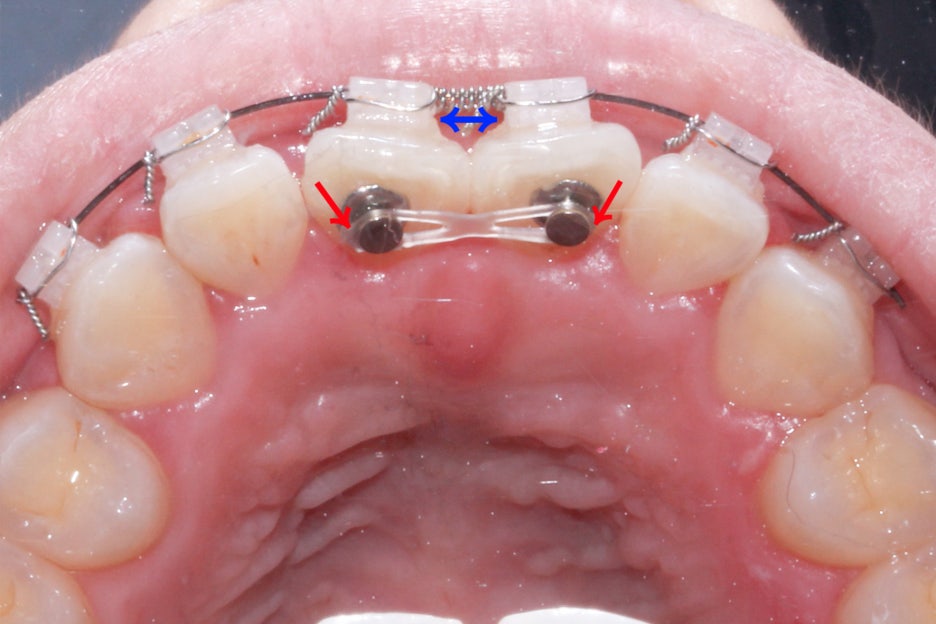

옥니교정을 위해서 지난 5개월 간 위와 같은

장치를 사용하여 중절치의 치축을 돌리는 과정을 진행하였는데요,

뻐드러진 중절치의 바깥면을 설측으로 당겨오기 위해

파워체인을 걸어 당기는 힘을 지속적으로 가하였습니다.

또한 중절치가 마주보고 있는 부분은 오픈코일스프링을 사용하여

공간을 넓혀주어 치열이 자연스러운 U자 모양을 형성할 수 있도록 하였는데요,